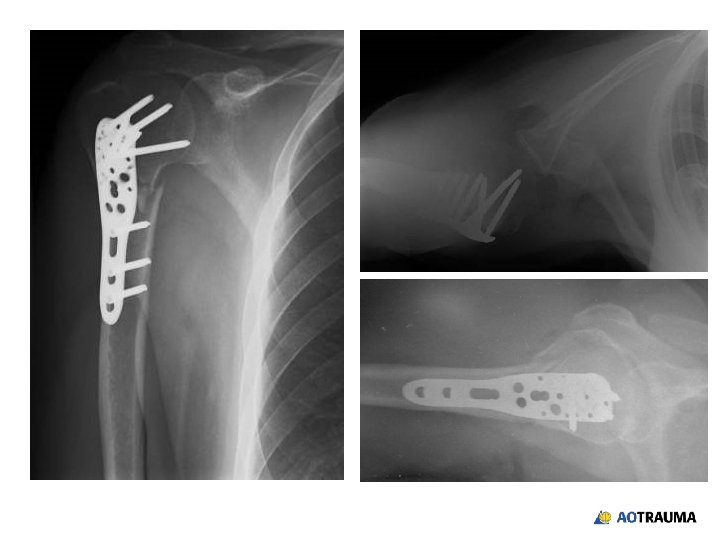

58 -year-old female, pedestrian hit by car • Housewife • Nondominant extremity • Closed isolated injury • Neurovascular status ok

After closed reduction in ER

What treatment options would you offer? 1. ORIF with standard plates 2. ORIF with locked plates 3. Screw fixation 4. Hemiarthroplasty 5. Other

postoperative x-rays